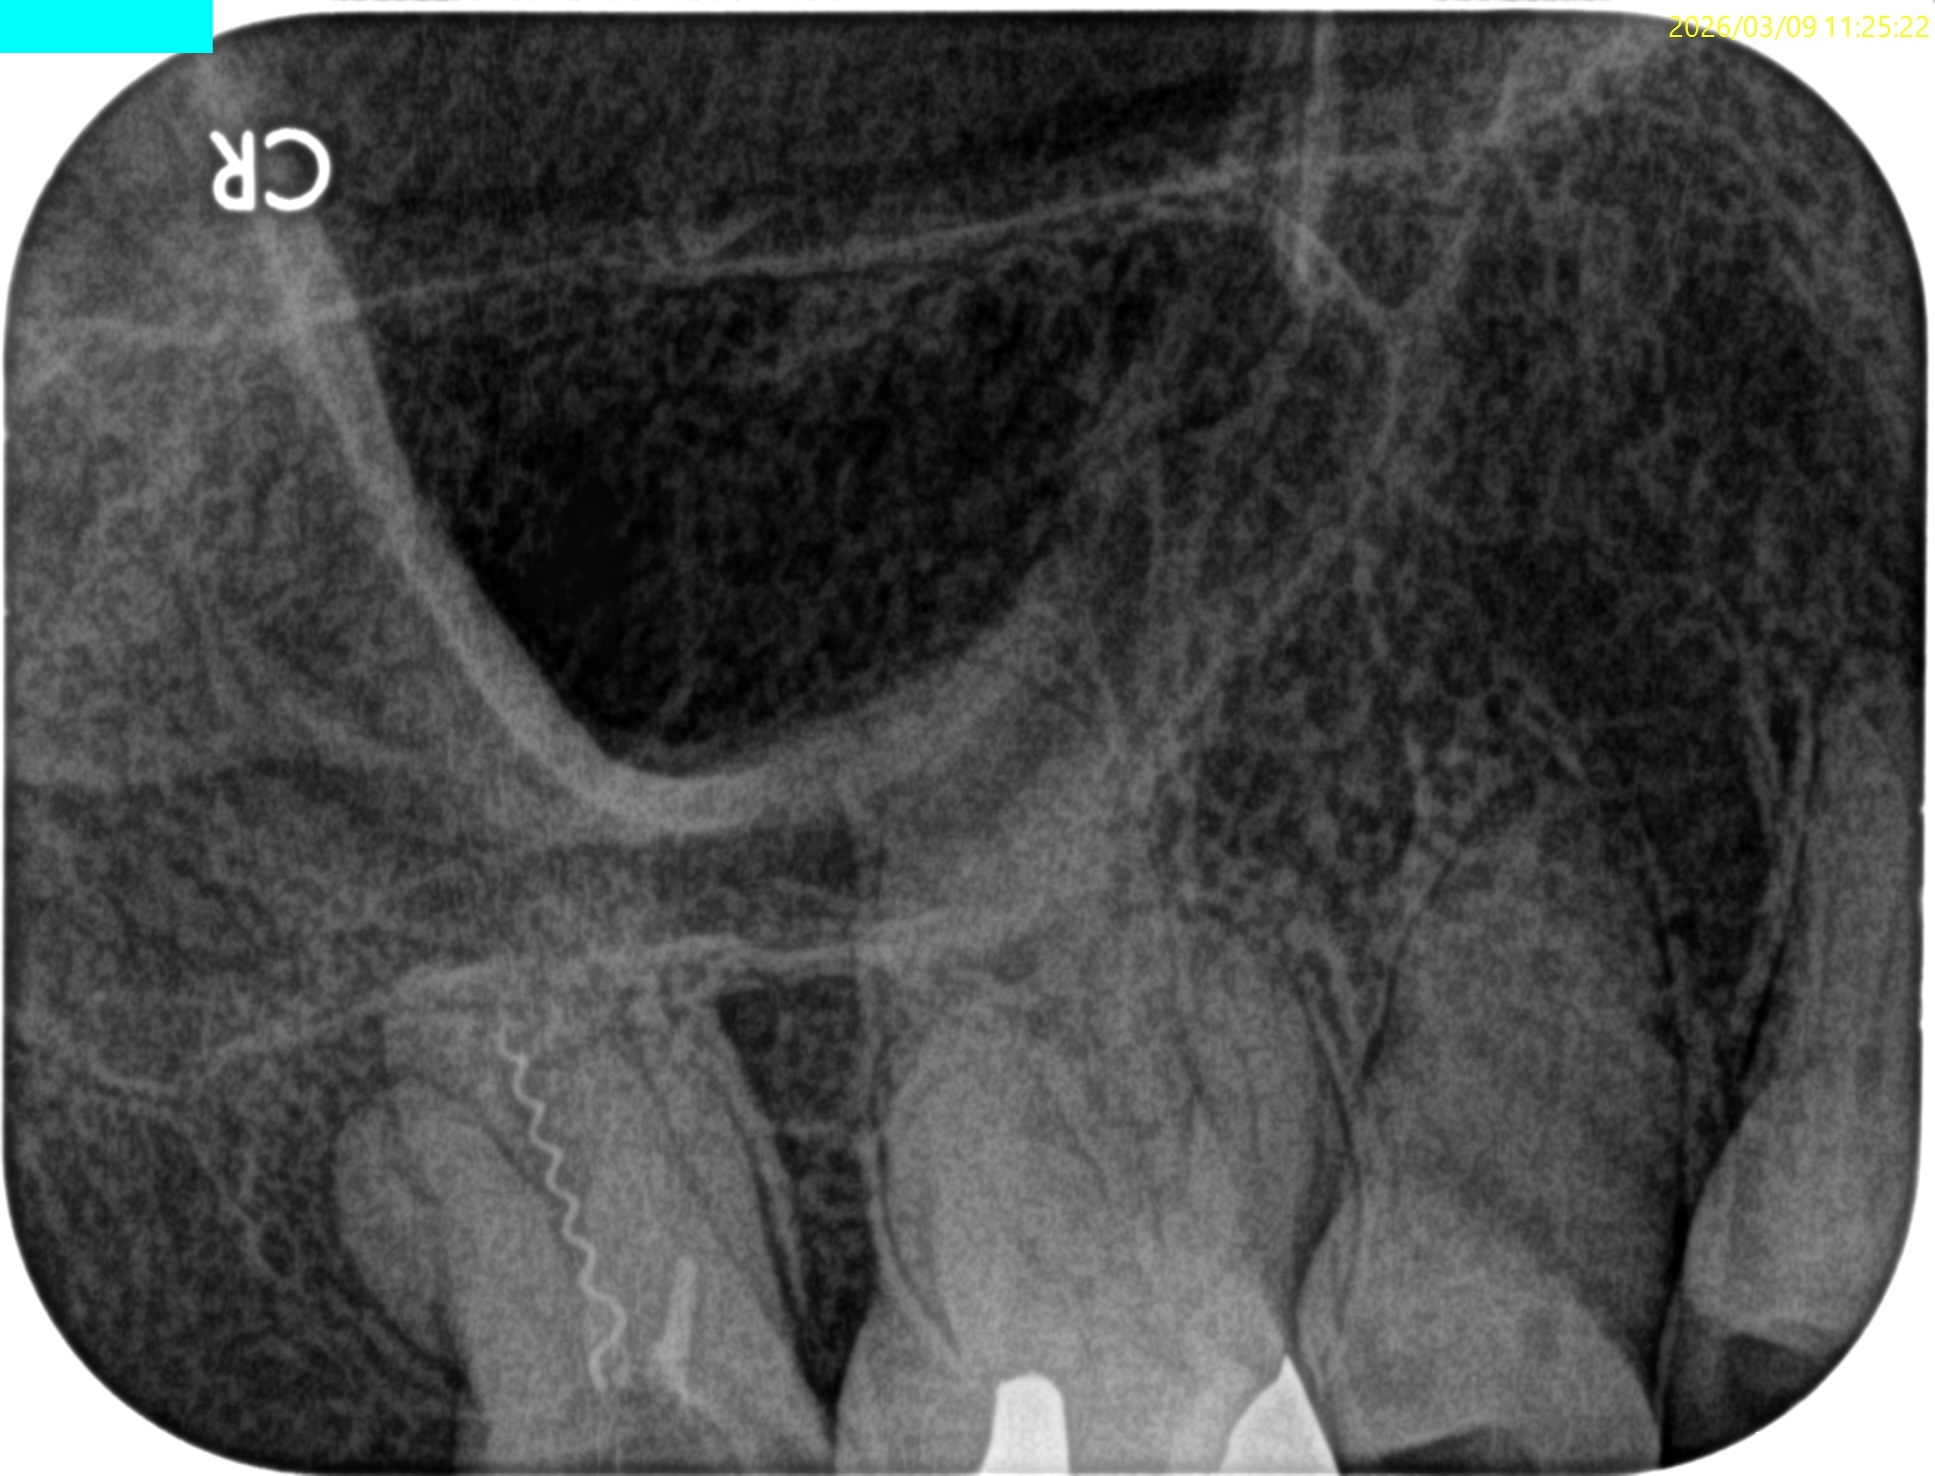

Pre-op Endo test(2026.3.9)

#2

MB, DB, Pともに石灰化している。

DBは根管口自体がどこにあるか?判然としない。

予測では、

MBのGutta Percha Pointの近傍にそれはありもしかすると石灰化しているかもしれない。

その際は3mm~4mm程度削合する必要があるかもしれない。

また、Pはレンツロが破断してしまい、前医(紹介歯科医院ではない)は知らん顔している。

根尖病変があり頬側歯槽骨が穿孔しているDB, レンツロが破断しており根尖病変があるPをSelectiveに再根管治療するという方針を術前に決定した。

Pre-op Endo Diagnosis(2026.3.9)

Pulp Dx: Previously initiated therapy

Periapical Dx: Symptomatic apical peridontitis

Recommended Tx: Re-RCT

根管充填後にPA, CBCTを撮影した。

DB

P

問題はないだろう。